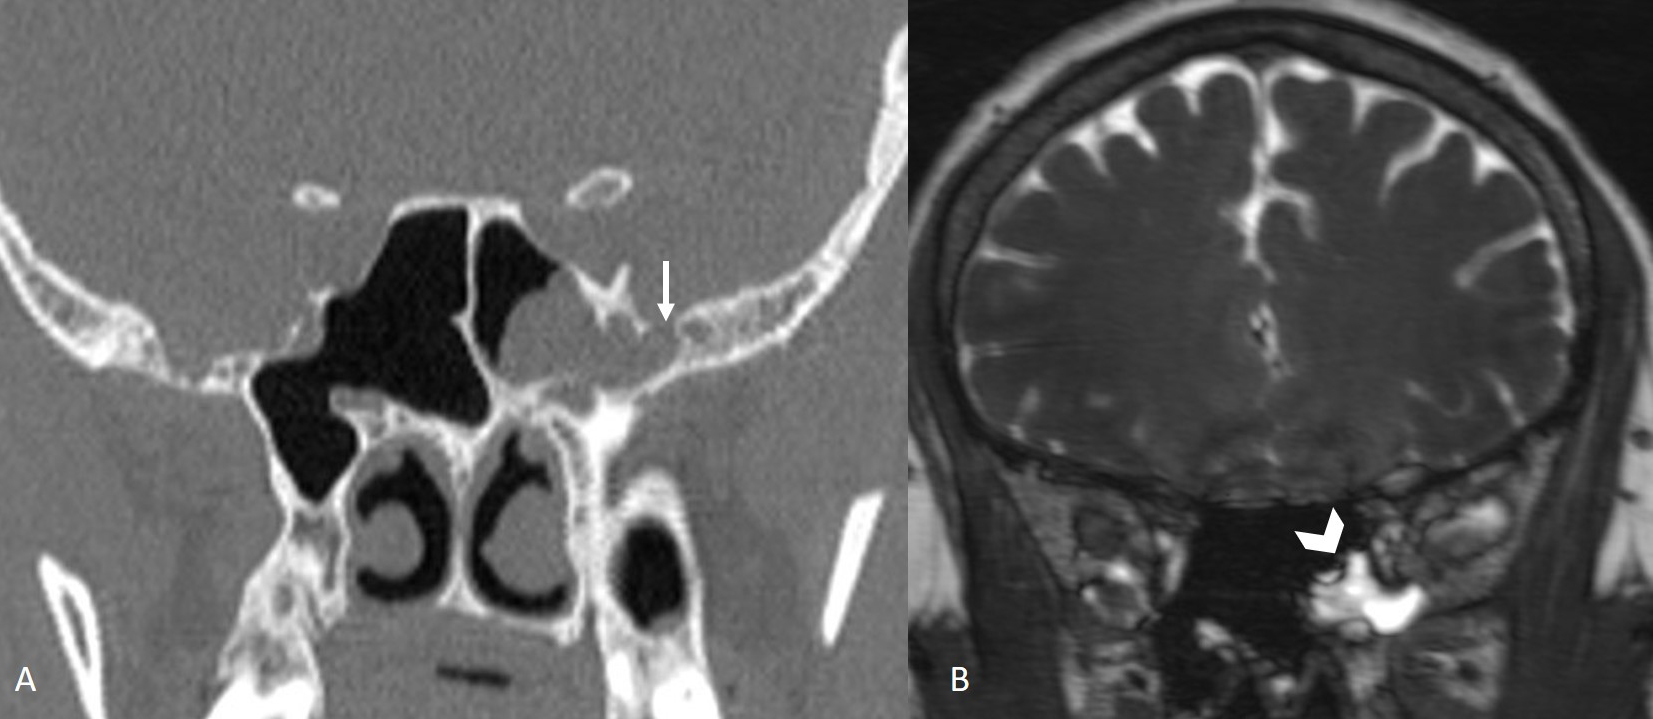

The institutional review board approved this single-center retrospective study. Patients with suspected CSF leakage who underwent MRI with a special protocol between 2012 and 2023 were evaluated. Images of 240 consecutive patients were assessed for CSF leakage by two neuroradiologist with 10 and 3 years of experience. Patients with leakage from sites other than the sphenoid sinus were excluded from the study (n = 220). Six out of 20 patients with a history of trauma or surgery of the sphenoid sinüs or cavernous sinus were also excluded. The remaining 14 patients with sphenoid sinüs CSF leakage formed the study group. Leakage was supported by surgical findings and beta-2 transferrin test. All imaging was performed using 3 Tesla (Verio, Siemens, Erlangen, Germany) or 1.5 Tesla (Aera, Siemens, Erlangen, Germany) MR scanners. The MRI protocol for CSF leakage consisted of T2 weighted fat suppressed coronal plane images with 3 mm slice thickness, T2-weighted sagittal plane SPACE images with 1 mm slice thickness, and CISS coronal plane images with 1 mm slice thickness. All images were evaluated by two radiologist with 4 years of experience in terms of empty sella, enlargement of the Meckel's caves (Figure 1), fluid in the optic nerve sheaths, vertical tortuosity of the optic nerves (Figure 2), arachnoid pits, encephaloceles (Figure 3), and lateral recess pneumatization of the sphenoid sinuses. Lateral recess pneumatization was defined as pneumatization lateral to the line connecting the foramen rotundum and the Vidian canal (Figure 4). The side of the leakage and the other accompanying sites of leakage were noted. The presence of a bony defect was evaluated on CT images (Figure 5).Descriptive statistics were used for data analysis. Continuous variables were presented as mean ± standard deviation [median (minimum?maximum)], and categorical variables were expressed as frequency and percentage.

Figure 5: Coronal CT image (A) shows bony defect (arrow) in the left sphenoid sinus lateral wall and coronal CISS image (B) show CSF (arrowhead) in the left sphenoid sinus. |

Twelve patients had undergone CT before MRI, and in 10 of these cases, a bony defect was identified on CT at the site of the CSF leak.